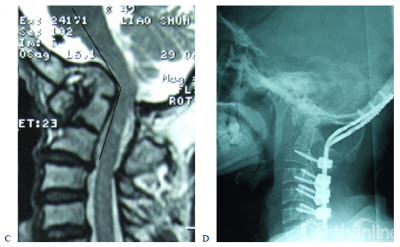

图1. 女,50岁,合并颈2/3分节不全,类风湿关节炎病史13年。A,术前X片示齿突向头侧移位,突入枕骨大孔内;B,术前CT示寰枢关节间异常骨性连接,齿突向上移位,超过McRae线7.02mm;C,术前T2加权MRI示上颈髓受压,CMA为109度; D,E术后X片及CT示齿突复位,低于McRae线9.89mm;F,G术后3年CT及三维重建示齿突复位得到维持,枕颈牢固融合;H,术后3年T1加权MRI示上颈髓受压解除,CMA改善到到155度。